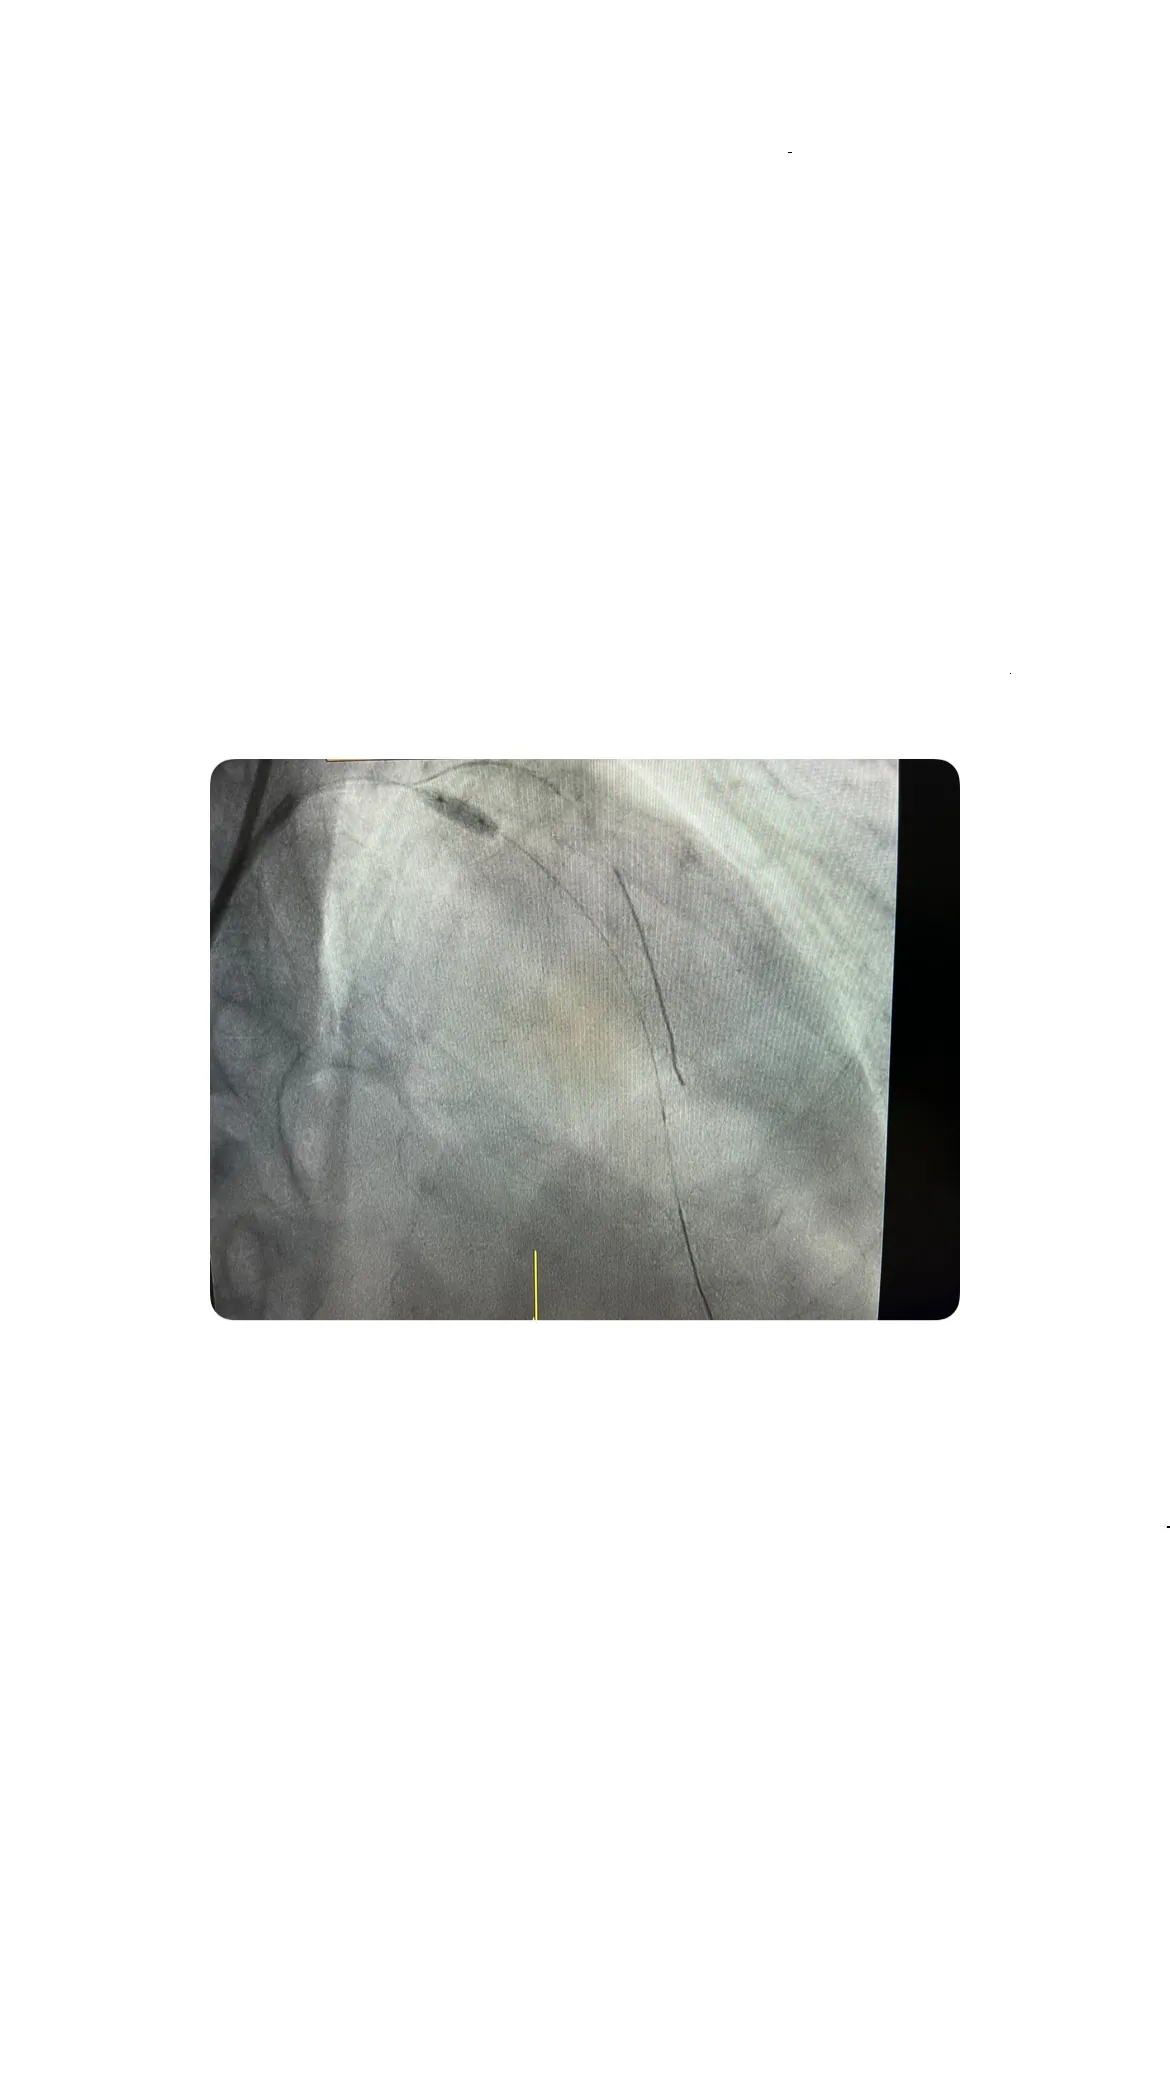

Uso de la guía de presión para valorar la severidad de la lesión

La guía de presión es un dispositivo que permite medir la presión dentro de las arterias coronarias y evaluar la severidad de una lesión. En este caso, la guía de presión arrojó un resultado positivo, lo que indicaba que la lesión en la coronaria izquierda era significativa y requería tratamiento. Esta confirmación fue crucial para proceder con la intervención adecuada y evitar un posible infarto.

Interpretación del resultado positivo de la guía de presión